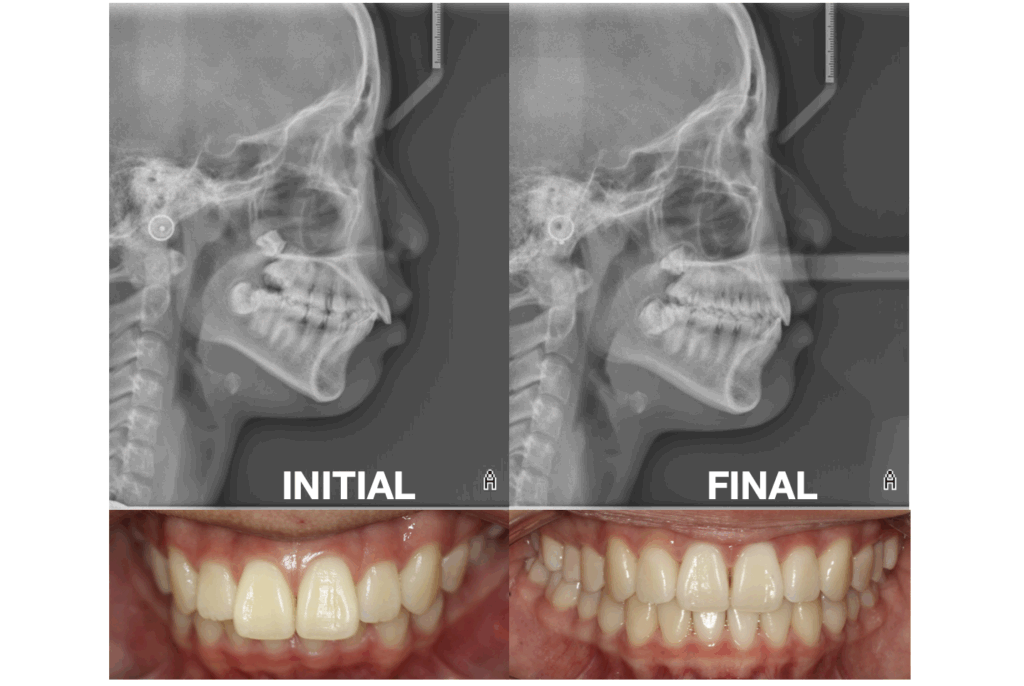

OBJECTIVE: Her exam revealed a half cusp Class II molar and canine relationship on both sides. She had excess overjet (5mm) and a deep bite (5mm). Both upper and lower incisors were proclined and protrusive relative to their skeletal bases. Her lips were full, protrusive to the E-plane, and she demonstrated lip-incompetence (evidenced by the flattened mentalis region - chin - on her ceph).

The patient had excellent Class II correction which helped decrease the overjet. Her compliance resulted in phenomenal retroclination and relative retraction of the upper and lower incisors. With the incisor movement, her lips became less protrusive and more competent (as evidenced by the decreased mentalis strain at her chin in the lateral ceph). During retroclination it is easy to deepen the bite inadvertently from “relative extrusion”, however her overbite was ideal upon completion.